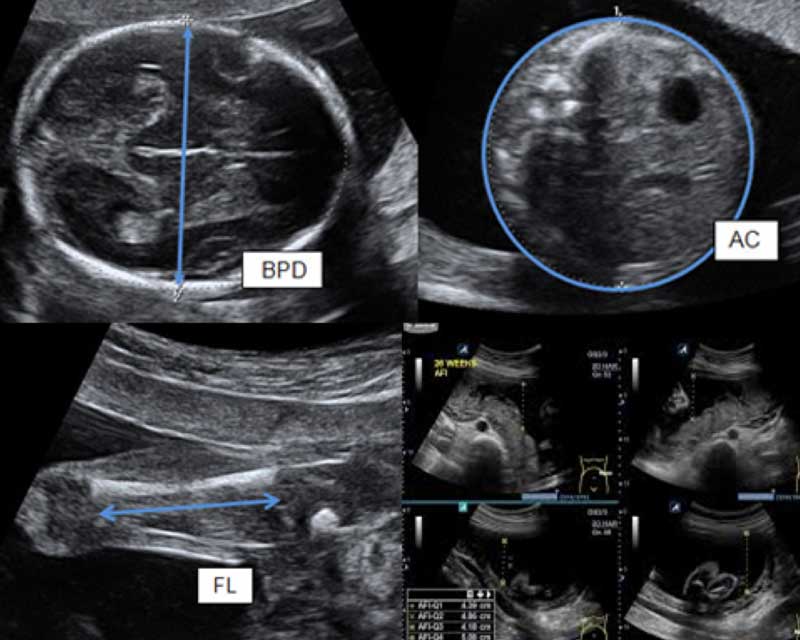

![[Ads] Ultrasound Baby Scan 4 2d ultrasound scan cheras](https://klinikazurose.com/wp-content/uploads/2022/03/2D-Growth-Klinik-Azurose.jpg)

As your baby grows, regular monitoring ensures everything is progressing well. A 2D Growth Scan allows you to track your baby’s development, measure key growth markers, and get professional guidance throughout your pregnancy.

A 2D ultrasound is the standard procedure used during obstetric ultrasound. It is the one used to produce 2 dimensional images of what is happening inside the mothers and baby’s body. Generally, all pregnancy ultrasounds are still done using 2D technology. A baby’s gestation, growth, heartbeat, development and size can all be seen clearly using 2D ultrasound. The position of the placenta, cord and lie/position of the baby can also be clearly seen.

The images from a 2d ultrasound tend to be in black and white and have the same level of detail as a photographic negative. Depending on how the baby is lying and their position in the uterus, different images will be seen.